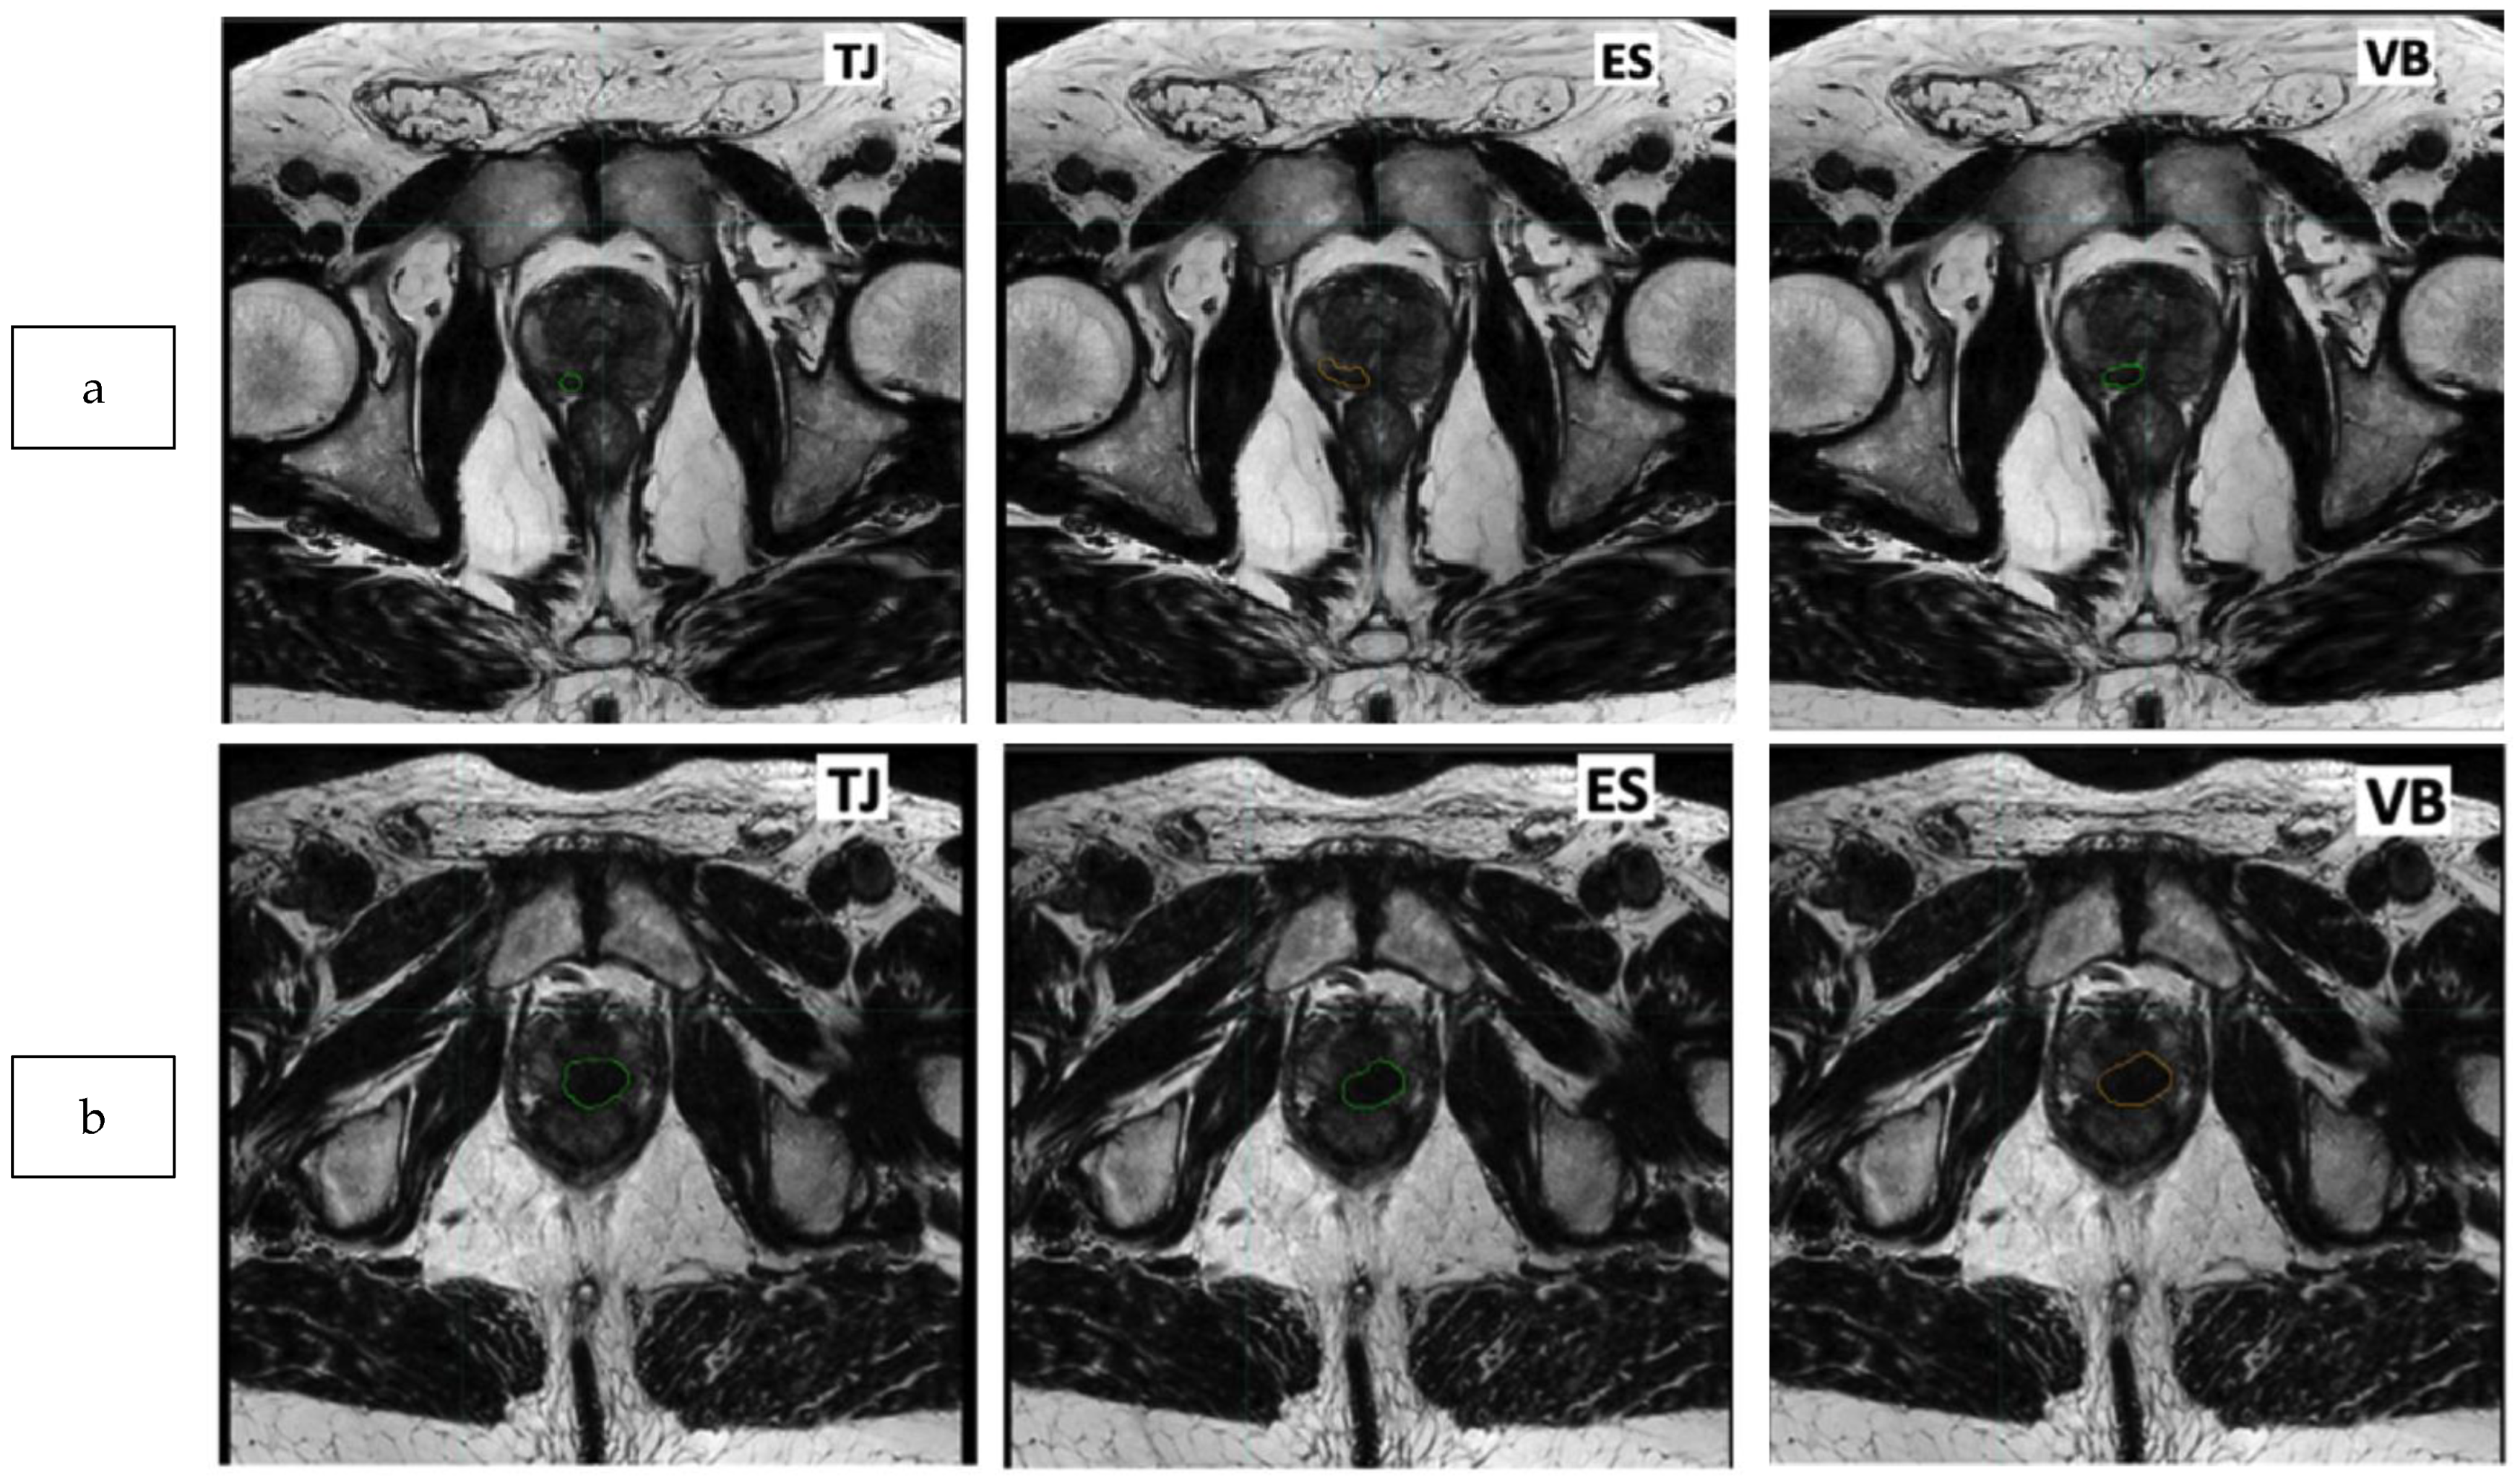

3.4. Impact of Tumoral Volume and PI-RADS Classification